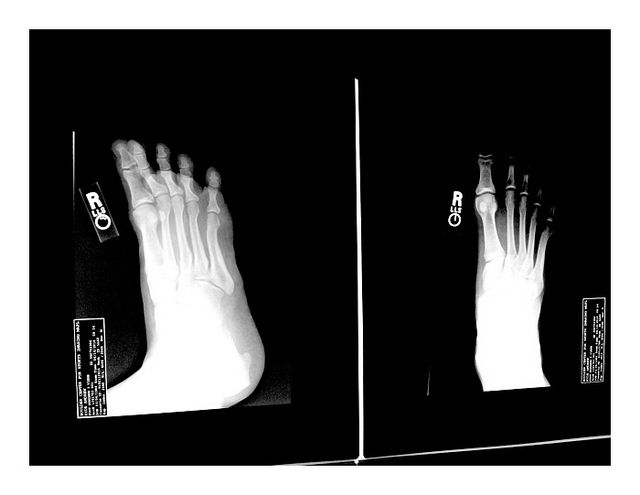

OLBERMANN: Badly. I fractured it very badly.  You've seen the five-toed running shoes?

OLBERMANN: Yes.  My foot doctor is the doctor for the Rockettes, which is an enviable job that I'm" sure many of us men would like to have.  What he said was these are the most wonderful shoes in the world to walk in.  And I noticed this a year ago when I first put them on.  They're great for you knees.  They're great for your hips.  They make you actually feel like you're younger like can walk again. You're not old guys.  Unfortunately, if you try to run in them and you weigh more than 175 lbs., you will break something.  This does not say this on the side of the box.  And as he said, I hate to tell you this in your late stage of life here but you're not less than 175 lbs.  So walk to your hearts content but don't run in them.

So it seems Keith Olbermann may have run too much too fast in his toe shoes, he got a stress fracture, and his podiatrist (who I suppose we should be impressed with, as he works with the Rockettes?), drew a line in the sand that if you're above 175 lbs., you can't run in Vibrams.